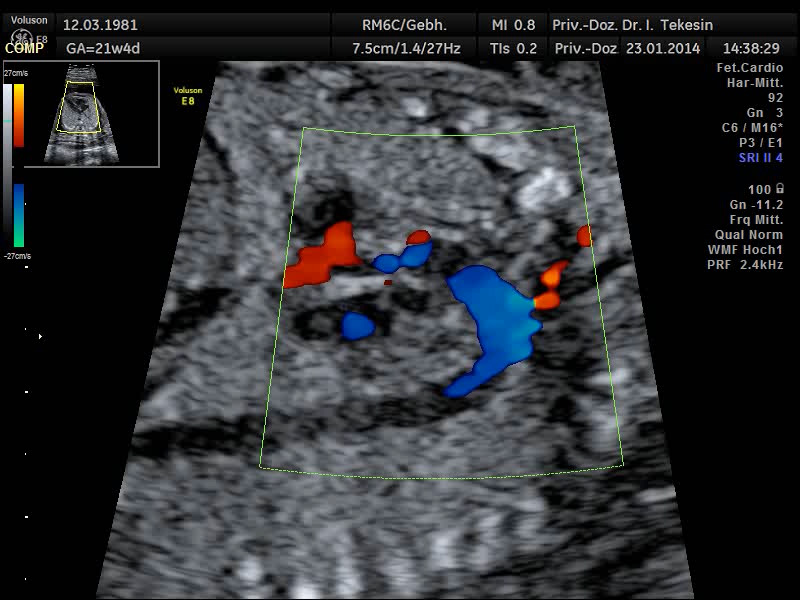

Normaler Vierkammer–Blick mit Farbe

Normaler Vierkammer-Blick mit Farbe

Aortenbogen in Farbe